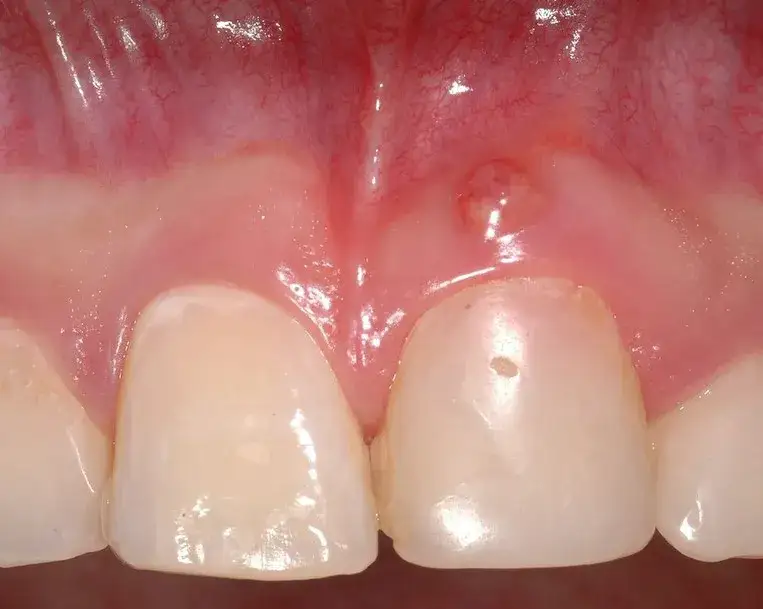

Ropna wydzielina to jeden z najbardziej widocznych symptomów. Może pojawić się w postaci małego guzka na dziąśle, z którego wydobywa się ropa. Inne objawy to nieprzyjemny zapach z ust, gorączka oraz ogólne osłabienie. Jeśli zauważysz te symptomy, nie zwlekaj z wizytą u dentysty.Przyczyny powstawania przetoki zęba: co prowadzi do stanu zapalnego